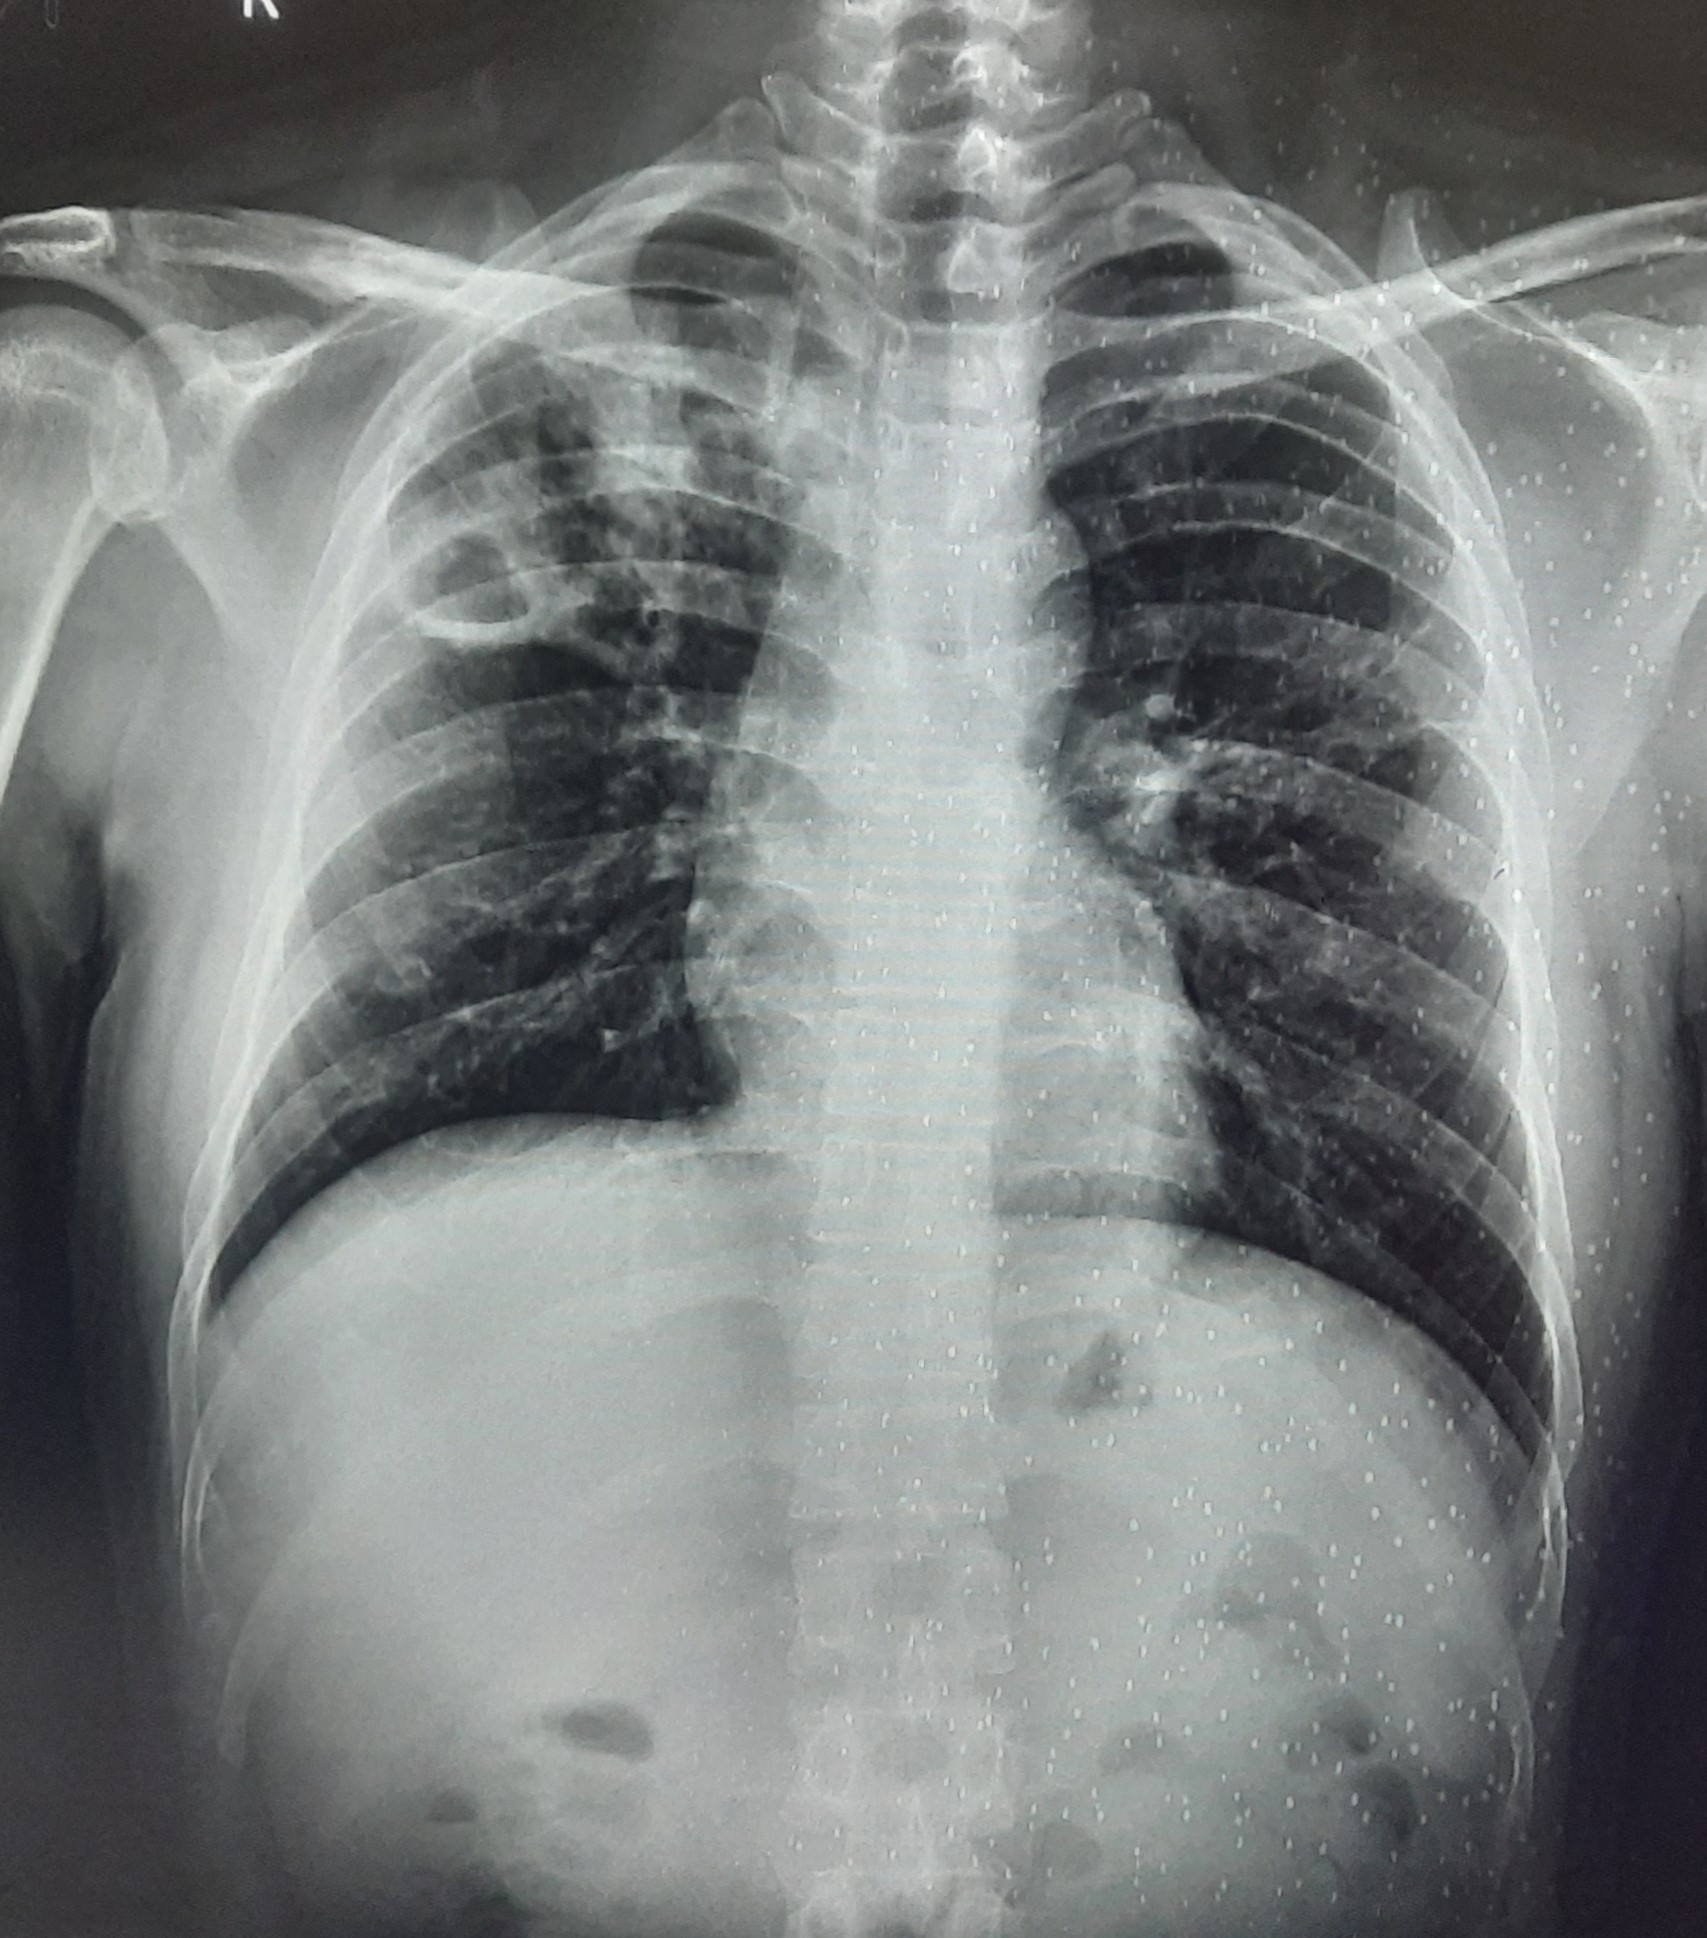

| 201 | IGGMC, Nagpur, Nagpur | P2 | 29-4271 | BUSHRA KHAN | Consent taken on Paper | 21 Yrs. |

Provisional Diag : PTB?

Final Diag : RIGHT SIDED CLINICALLY DIAGNOSED TUBERCULAR PLEURAL EFFUSION |

TB Case (Confirmed) | RIGHT SIDED PLEURAL EFFUSION | Abnormality visible on x-ray |